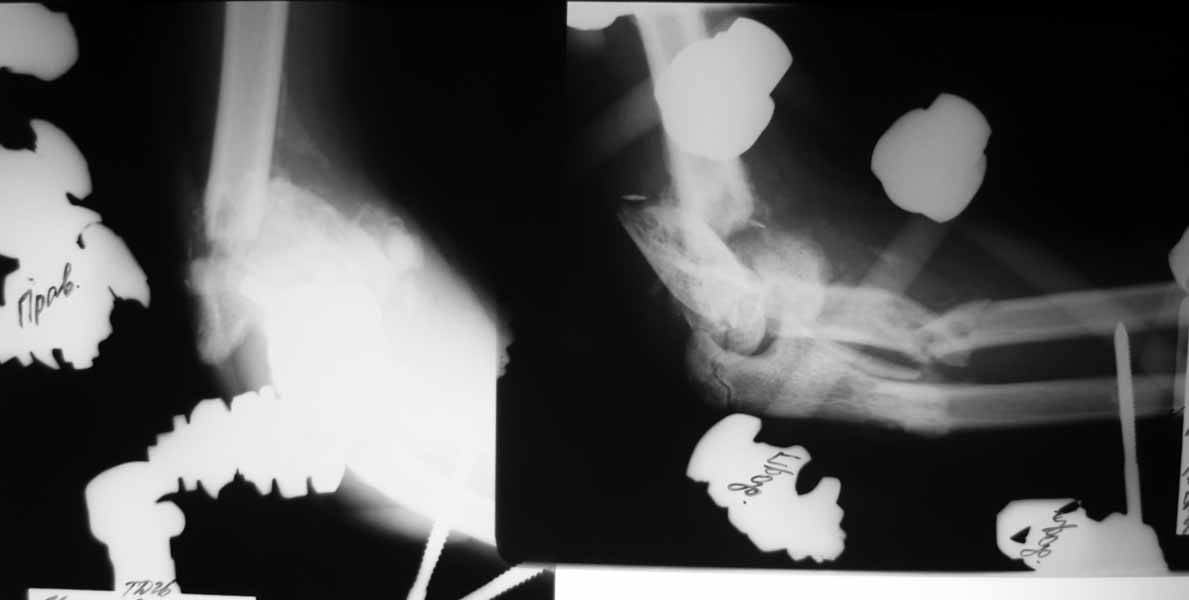

Прошу простить за задержку - не было линии. Шлю снимки.

|

Судя по рентгенограммам Вашей пациентки сустав далеко еще не потерян, особенно у ребенка. Вообще локтевой сустав очень толерантен к плохой репозиции. Рентгенограммы бывают после консолидации ужасными, а функция очень хорошей. Если возможно выложите рентгенограммы локтевого сустава на данный момент, после ПХО. На АСАМИ видел методику леченая таких повреждений в спице стержневом аппарате с ранним началом движенийы. Да получается плохая репозиция, но сустав хорошо работает.